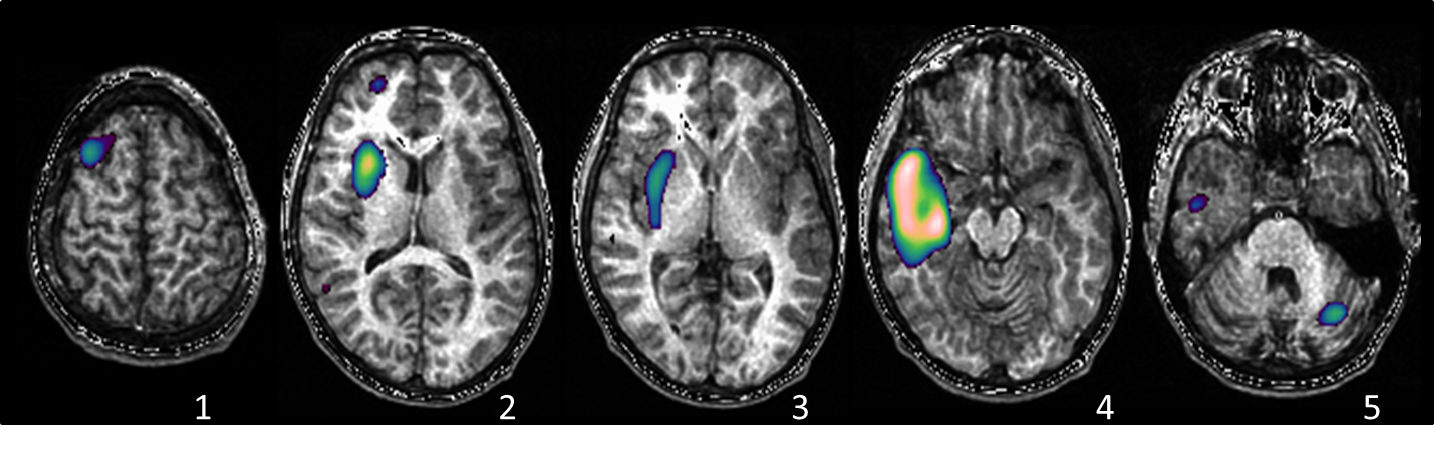

© UMR1129 CEA - SPECT ictal : le foyer épileptique

et sa propagation chez un enfant de 10 ans avec épilepsie temporale